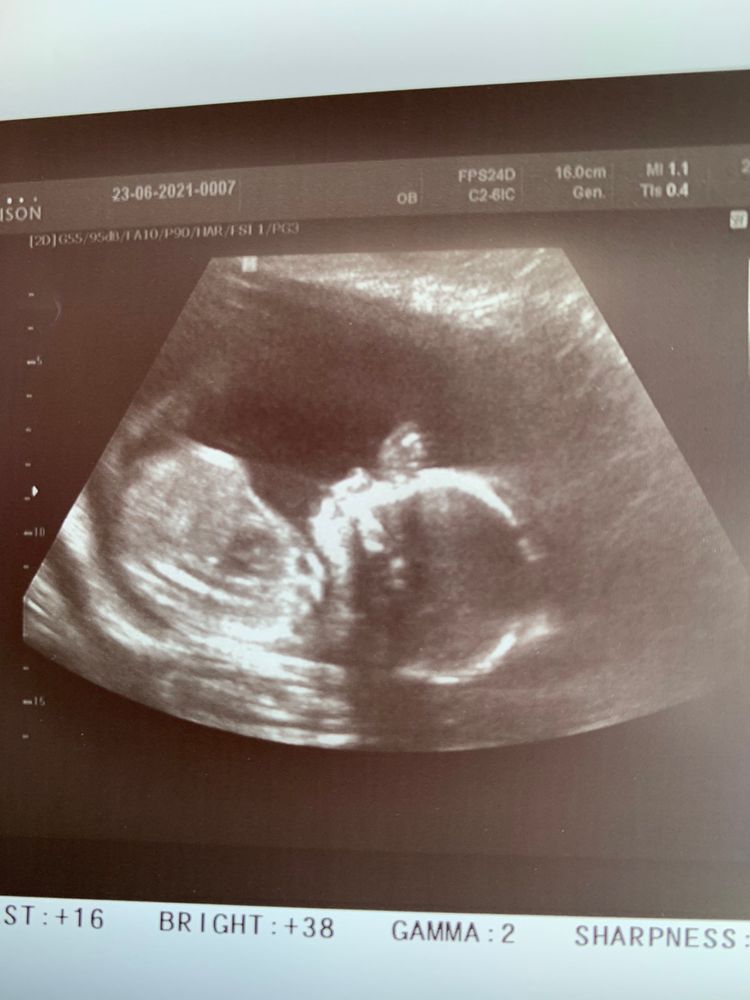

Ну вот нам 20 недель сделали второй скрининг нашего сыночка!!!;)

Все совпадает по срокам . Токсикоз так же ещё у нас присутствует по утрам. Животик уже приличный вес малыша 333 грамм))) на УЗИ мы потягушки делали ))

Мира, хахха мой потягивался и руку за головкой держал )))) интересно так)